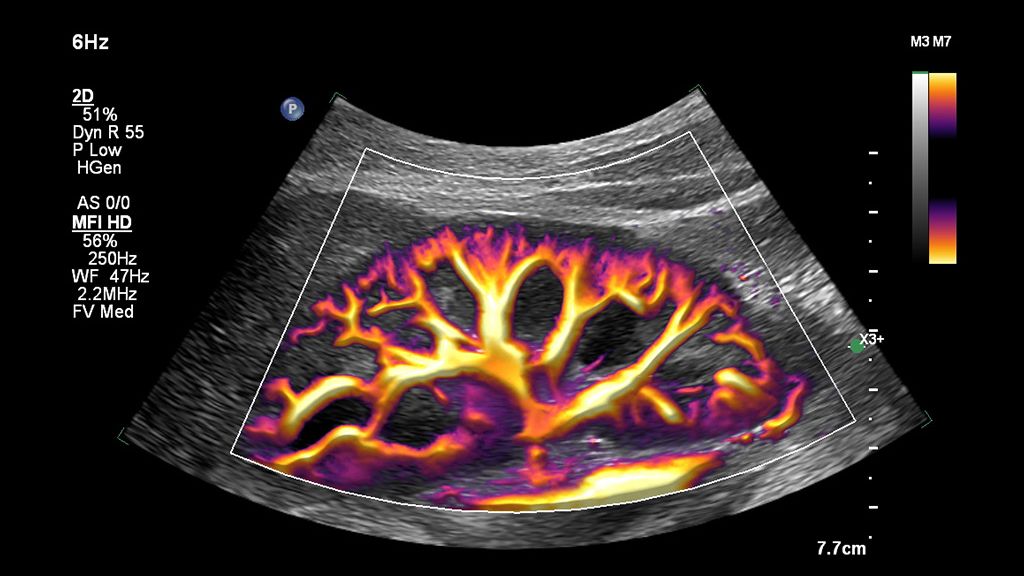

The widespread use of this technology in a general population could be helpful in screening for advanced chronic liver disease, especially considering that a complete study can be done in under three minutes using a non-invasive method for chronic liver disease.